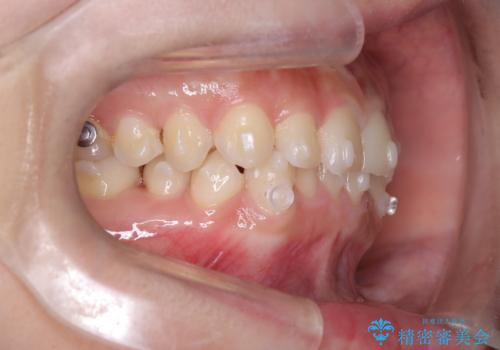

- インビザライン

- 前歯のガタガタが気になるとのことでご相談いただきました。診察すると、歯列のスペースが不足し、前歯が重なっている状態でした。抜歯をせずに整えるため、歯と歯の間をわずかに削るIPR(歯列幅径削除)と、奥歯を後方へ動かす遠心移動を組み合わせてスペースを確保しながら並べる治療計画を立てました。

インビザラインを用いて歯を少しずつ移動させながら、IPRで微調整を行い、スペースを確保しました。また、奥歯を遠心移動させることで、前歯を自然な位置に並べることができました。治療後は、「ガタガタがなくなり、スムーズな歯並びになった」と患者様にもご満足いただきました。